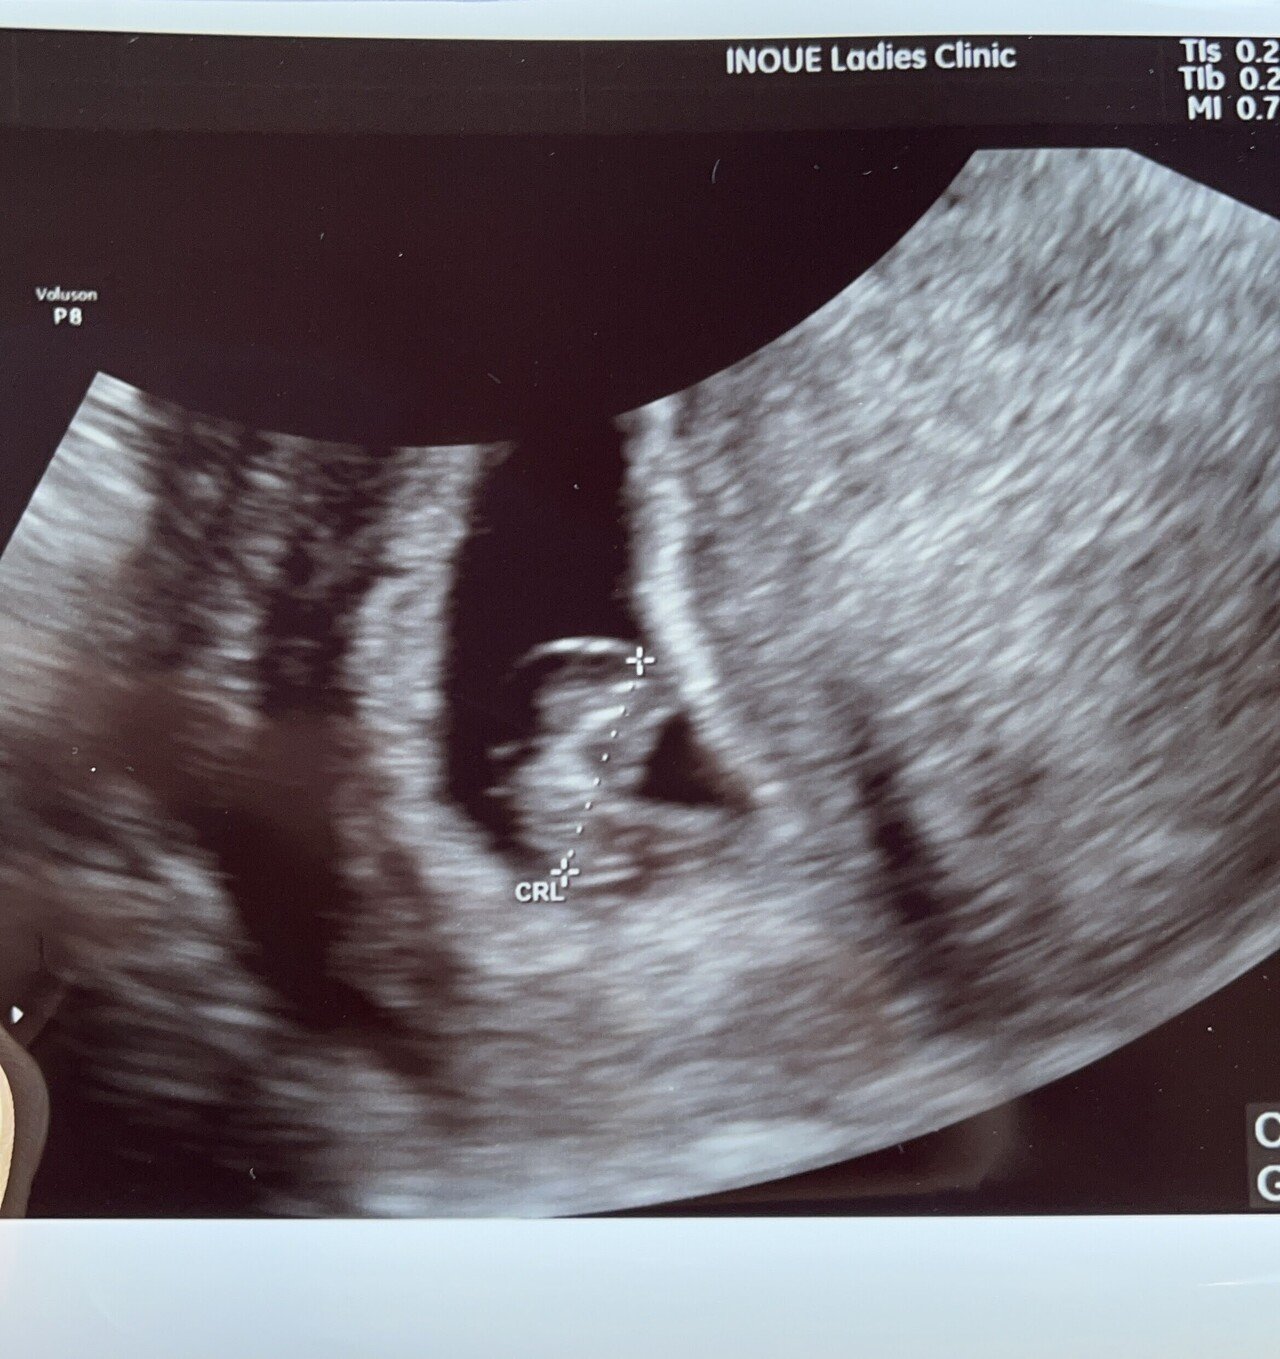

7週1日 再び病院へ 妊婦はつらいよ

胎嚢や胎芽が確認できない原因としては、下記のことが考えられます。 ① 受診の時期が早すぎる 超音波検査で胎嚢や胎芽が見えない場合、受診の時期が早すぎることがあります。 現在の妊娠検査薬 (結論)妊娠7週で心拍確認できない=その後100%流産ではない。 ただし、条件あり この調査結果に限れば、妊娠7週中に心拍が確認できなくても 自然妊娠なら過度に心配する必要は

胎芽が見えない。 妊娠7週ぐらいです。 胎芽が見えない。 掲載日 13年8月25日 更新日 16年1月日 はじめまして。 初妊娠で7週目ぐらいで、昨日三回目の検診でした。 昨日の検診で心拍妊娠2ヶ月(妊娠4週、5週、6週、7週)の胎児と母体の状態 妊娠4週になると見えてくる、「胎嚢」って何? 「卵黄嚢」って? 妊娠5週になると脳や神経、心臓など臓器の原型ができて、手足や目 妊娠7週 胎芽確認出来ない 1818 生理周期から数えて現在妊娠7週です。 5週の時点で卵嚢確認出来、一週間後6週で卵嚢の大きさから妊娠5w2dと診断されました。 そし

22年1月25日 IKURICH編集部 7週の胎芽の大きさってどれくらいなのか? お腹の赤ちゃんの成長を気にされている妊娠7週目のママは多いのではないでしょうか? お腹の赤ちゃ